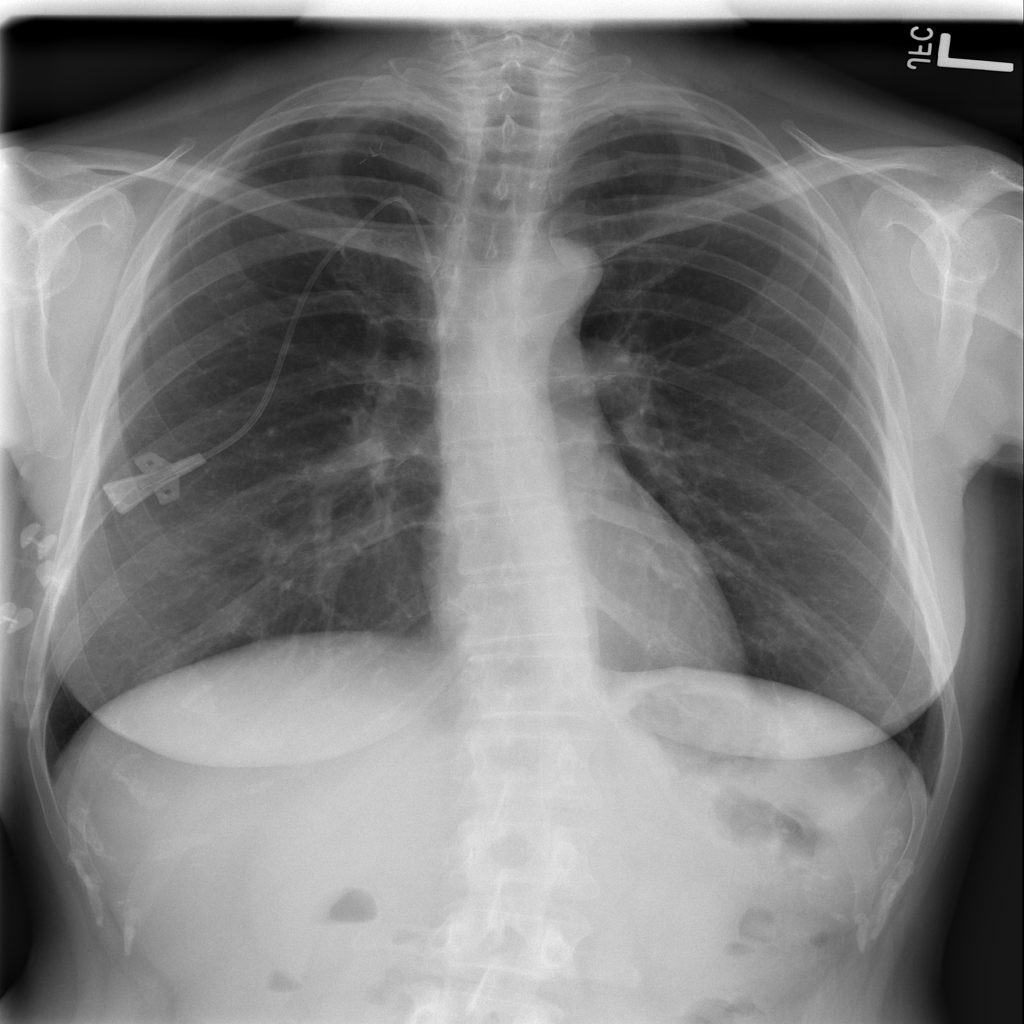

Once the SARS-COV2 reaches the host at the lung, it gets into the cells through a protein called ACE2, which serves as the ”opening” of the cell lock. After the genetic material of the virus has multiplied, the infected cell produces proteins that complement the viral structure to produce new viruses. Then, the virus destroys the infected cell, leave it and infect new cells. The destroyed cells produce radiological lesions [5, 6, 7] such as consolidations and nodules in the lungs, that are observable in the form of ground-glass opacity regions in the XR images (Fig. 1c). These lesions are more noticeable in patients assessed or more days after the onset of the disease, and especially in those older than [8]. Findings also suggest that patients recovered from COVID-19 have developed pulmonary fibrosis [9], in which the connective tissue of the lung gets inflamed. This leads to a pathological proliferation of the connective tissue between the alveoli and the surrounding blood vessels. Given the aforementioned, radiological imaging techniques –using plain chest X-Ray (XR) and/or thorax Computer Tomography (CT)– have become crucial diagnosis and evaluation tools to identify and assess the severity of the infection.

The areas of significant interest used by the CNN for discrimination purposes are identified using a qualitative analysis based on a Gradient-weighted Class Activation Mapping (Grad-CAM) [38]. This is an explainability method that serves to provide insights about the manners on how deep neural networks learn, pointing to the most significant areas of interest for decision-making purposes. The method uses the gradients of any target class to flow until the final convolutional layer, and to produce a coarse localization map which highlights the most important regions in the image identifying the class. The result of this method is a heat map like those presented in Fig. 1, in which the colour encodes the importance of each pixel in differentiating among classes.

The regions of interest identified by the network, were analyzed qualitatively using Grad-CAM activation maps [38]. Results shown by the activation maps, permit the identification of the most significant areas in the image, highlighting the zones of interest that the network is using to discriminate. In this regard, Fig. 1, presents examples of the Grad-CAM of a control, a pneumonia, and a COVID-19 patient, for each of the three experiments considered in the paper. It is important to note that the activation maps are providing overall information about the behaviour of the network, pointing to the most significant areas of interest, but the whole image is supposed to be contributing to the classification process to a certain extent.

The second row in Fig. 1 shows several prototipical results applying the Grad-CAM techniques to experiment 1. The examples show the areas of significant interest for a control, pneumonia and COVID-19 patient. The results suggest that the detection of pneumonia or COVID-19 is often carried out based on information that is outside the expected area of interest, i.e. the lung area. In the examples provided, the network focuses on the corners of the XR image or in areas around the diaphragm. In part, this is likely due to the metadata which is frequently stamped on the corners of the XR images. The Grad-CAM plots corresponding to the experiment 2 (third row of Fig 1), indicates that the model still points towards areas which are different to the lungs, but to a lesser extent. Finally, the Grad-CAM of experiment 3 (fourth row of Fig 1) presents the areas of interest where the segmentation procedure is carried out. In this case, the network is forced to look at the lungs, and therefore this scenario is supposed to be more realistic and more prone to generalizing as artifacts that might bias the results are somehow discarded.

This study evaluates a deep learning model for the detection of COVID-19 from RX images. The paper provides additional evidence to the state of the art, supporting the potentiality of deep learning techniques to accurately categorize XR images corresponding to control, pneumonia, and COVID-19 patients (Fig. 1). These three classes were chosen under the assumption that they can support clinicians on making better decisions, establishing potential differential strategies to handle patients depending on their cause of infection [17]. However, the main goal of the paper was not to demonstrate the suitability of the deep learning for categorizing XR images, but to make a thoughtful evaluation of the results and of different preprocessing approaches, searching for better explainability and/or interpretability of the results, while providing evidence of potential effects that might bias results.

We stand on the fact that automatic diagnosis is much more than a classification exercise, meaning that many factors have to be had in mind to bring these techniques to the clinical practice. To this respect, there is a classic assumption in the literature that the associated heat maps –calculated with techniques such as Grad-CAM– provide a clinical interpretation of the results, which is unclear in practice. In light of the results shown in the heat maps depicted in Fig. 1, we show that experiment 1 must be carefully interpreted. Despite the high-performance metrics obtained in experiment 1, the significant areas identified by the network are pointing towards certain areas with no clear interest for the diagnosis, such as corners of the images, the sternum, clavicles, etc. From a clinical point of view, this is clearly biasing the results. It means that other approaches are necessary to force the network to focus on the lungs area. To this respect, we have developed and compared the results with two preprocessing approaches based on cropping the images and segmenting the lungs area (experiment 2 and experiment 3). Again, given the heat maps corresponding to experiment 2, we also see similar explainability problems to those enumerated for experiment 1. Reducing the area of interest to that proposed in experiment 2 significantly decreases the performance of the system due to the removal of the metadata that usually appear in the top left and/or right corner, and to the removal of areas which are of interest to categorize the images but have no interest from the diagnosis point of view. However, while comparing experiment 2 and 3, performance results improve in the third approach, which focuses on the same region of interest but with a mask that forces the network to see only the lungs. Thus, results obtained in experiments 2 and 3 suggest that eliminating the needless features extracted from the background or non-related regions improves the results. Besides, the third approach (experiment 3), provides more explainable and interpretative results, with the network focusing its attention only in the area of interest for the disease. The gain in explainability of the last method is still at the cost of a lower accuracy with respect to experiment 1, but the improvement in explainability and interpretability are considered critical to translate these techniques to the clinical setting. Despite the decrease in performance, the proposed method in experiment 3 has provided promising results, with an Acc of , BAcc of , GMR of and AUC of .

The COVID-Net has also demonstrated being a good starting point for the characterization of the disease. Indeed, the outcomes of the paper suggest the possibility to automatically identifying the lung lesions associated with a COVID-19 infection (see Fig.1) by analyzing the Grad-CAM mappings of experiment 3, providing an explainable justification about the way the network works. However, the interpretation of the heat maps obtained for the control class must be carried out carefully. Whereas the areas of significant interest for pneumonia and COVID-19 classes are supposed to point to potential lesions (i.e. with higher density and/or with different textures in contrast to controls), the areas of significant interest for the classification in the control group are supposed to correspond to a sort of complement, potentially highlighting less dense areas. Thus, not meaning the presence of any kind of lesion in the lungs.